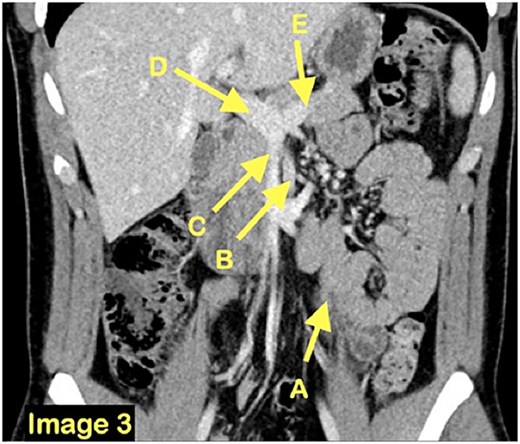

A 21-year-old man, with no medical or surgical history, presented to a community emergency department with a history of intermittent abdominal pain, accompanied by nausea and vomiting, worsened by meals. Initial blood tests and computed tomographic (CT) scan were deemed normal. However, given the discrepancy between the patient’s presentation and the normal paraclinical findings, he underwent a diagnostic laparoscopy. The small bowel was explored in its entirety and was found to be almost entirely located in a retroperitoneal fossa, on the left side of the ligament of Treitz, establishing the diagnosis of a left paraduodenal hernia. The hernia was reduced, and the defect left unrepaired. In the early post-operative period, the patient returned to the emergency department of a tertiary center with recurrent obstructive symptoms. A second CT scan (Figs 1–3) was performed and, on this occasion, a left paraduodenal hernia was identified. Retrospectively, this finding was also visible on the first imaging.

A coronal CT scan view demonstrating once again the clustered small bowel loops (A) and the surrounding vasculature inferior mesenteric vein (B), superior mesenteric vein (C), portal vein (D) and splenic vein (E).